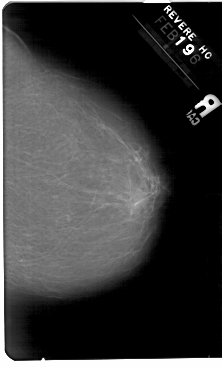

A_1346_1.RIGHT_CC

RIGHT_MLO LINES 5491 PIXELS_PER_LINE 3586 BITS_PER_PIXEL 12 RESOLUTION 43.5 NON_OVERLAY